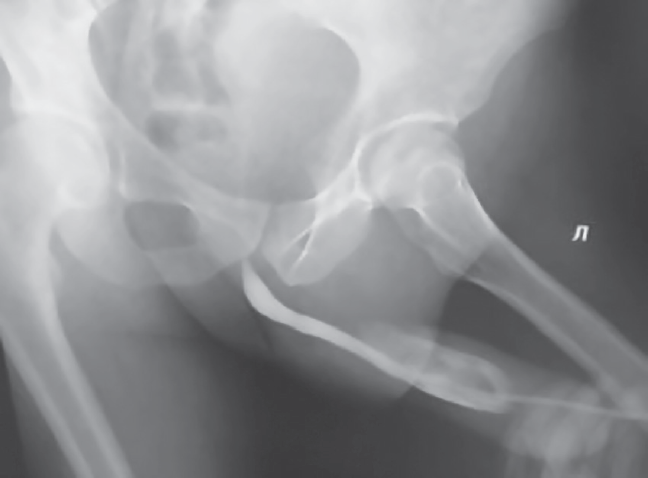

Больной Б., 28 лет, поступил в урологическое отделение Городской больницы № 4 г. Сочи в апреле 2018 г. с жалобами на боль в половом члене, синюшность кожи полового члена, отсутствие самостоятельного мочеиспускания. Травму получил около 20 часов назад во время полового акта. При УЗИ полового члена выявлена напряженная гематома полового члена, при ретроградной уретрографии — частичное повреждение висячего отдела уретры с распространением контрастного вещества в кавернозные тела (рис. 1). Диагноз: «Тупая травма полового члена (перелом) с повреждением уретры».

Рис. 1. Ретроградная уретрография до операции

Fig. 1. Retrograde urethrography before surgery